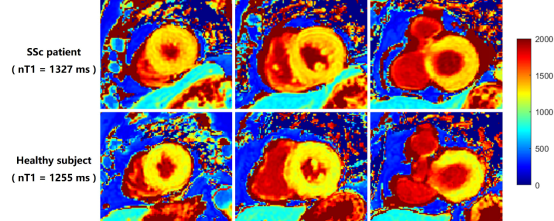

图1:SSc患者和健康受试者在CMR中测量的心肌nativeT1值。一名50岁SSc患者,DLCO下降(54%),心肌native T1升高(1327ms)。同时,图像(下图)显示了50岁健康受试者的心肌的nativeT1图,平均T1值为1255ms。心肌T1图的MR图像从左心室的短轴位扫描获得。nT1,nativeT1值。